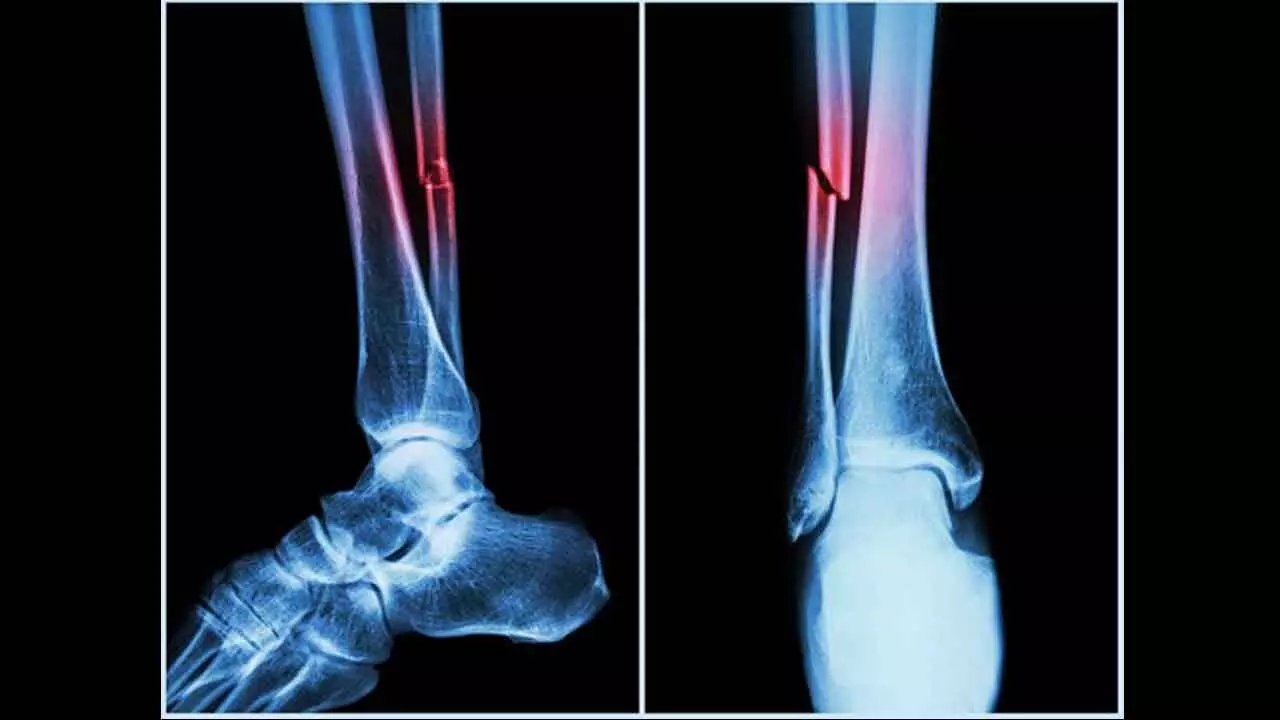

Further research by ECU's Marc Sim revealed that AAC is not only a cardiovascular risk indicator but also a strong predictor of falls and fractures. In fact, AAC outperformed traditional fall risk factors like bone mineral density and past fall history.

"The higher the calcification in your arteries, the higher the risk of falls and fractures," Sim said, adding clinicians typically overlook vascular health in fall assessments, and this algorithm changes that.

"Our analysis uncovered that AAC was a very strong contributor to fall risks and was actually more significant than other factors that are clinically identified as fall risk factors."

Sim said that the new machine algorithm, when applied to bone density scans, could give clinicians more information about the vascular health of patients, which is an under-recognised risk factor for falls and fractures.